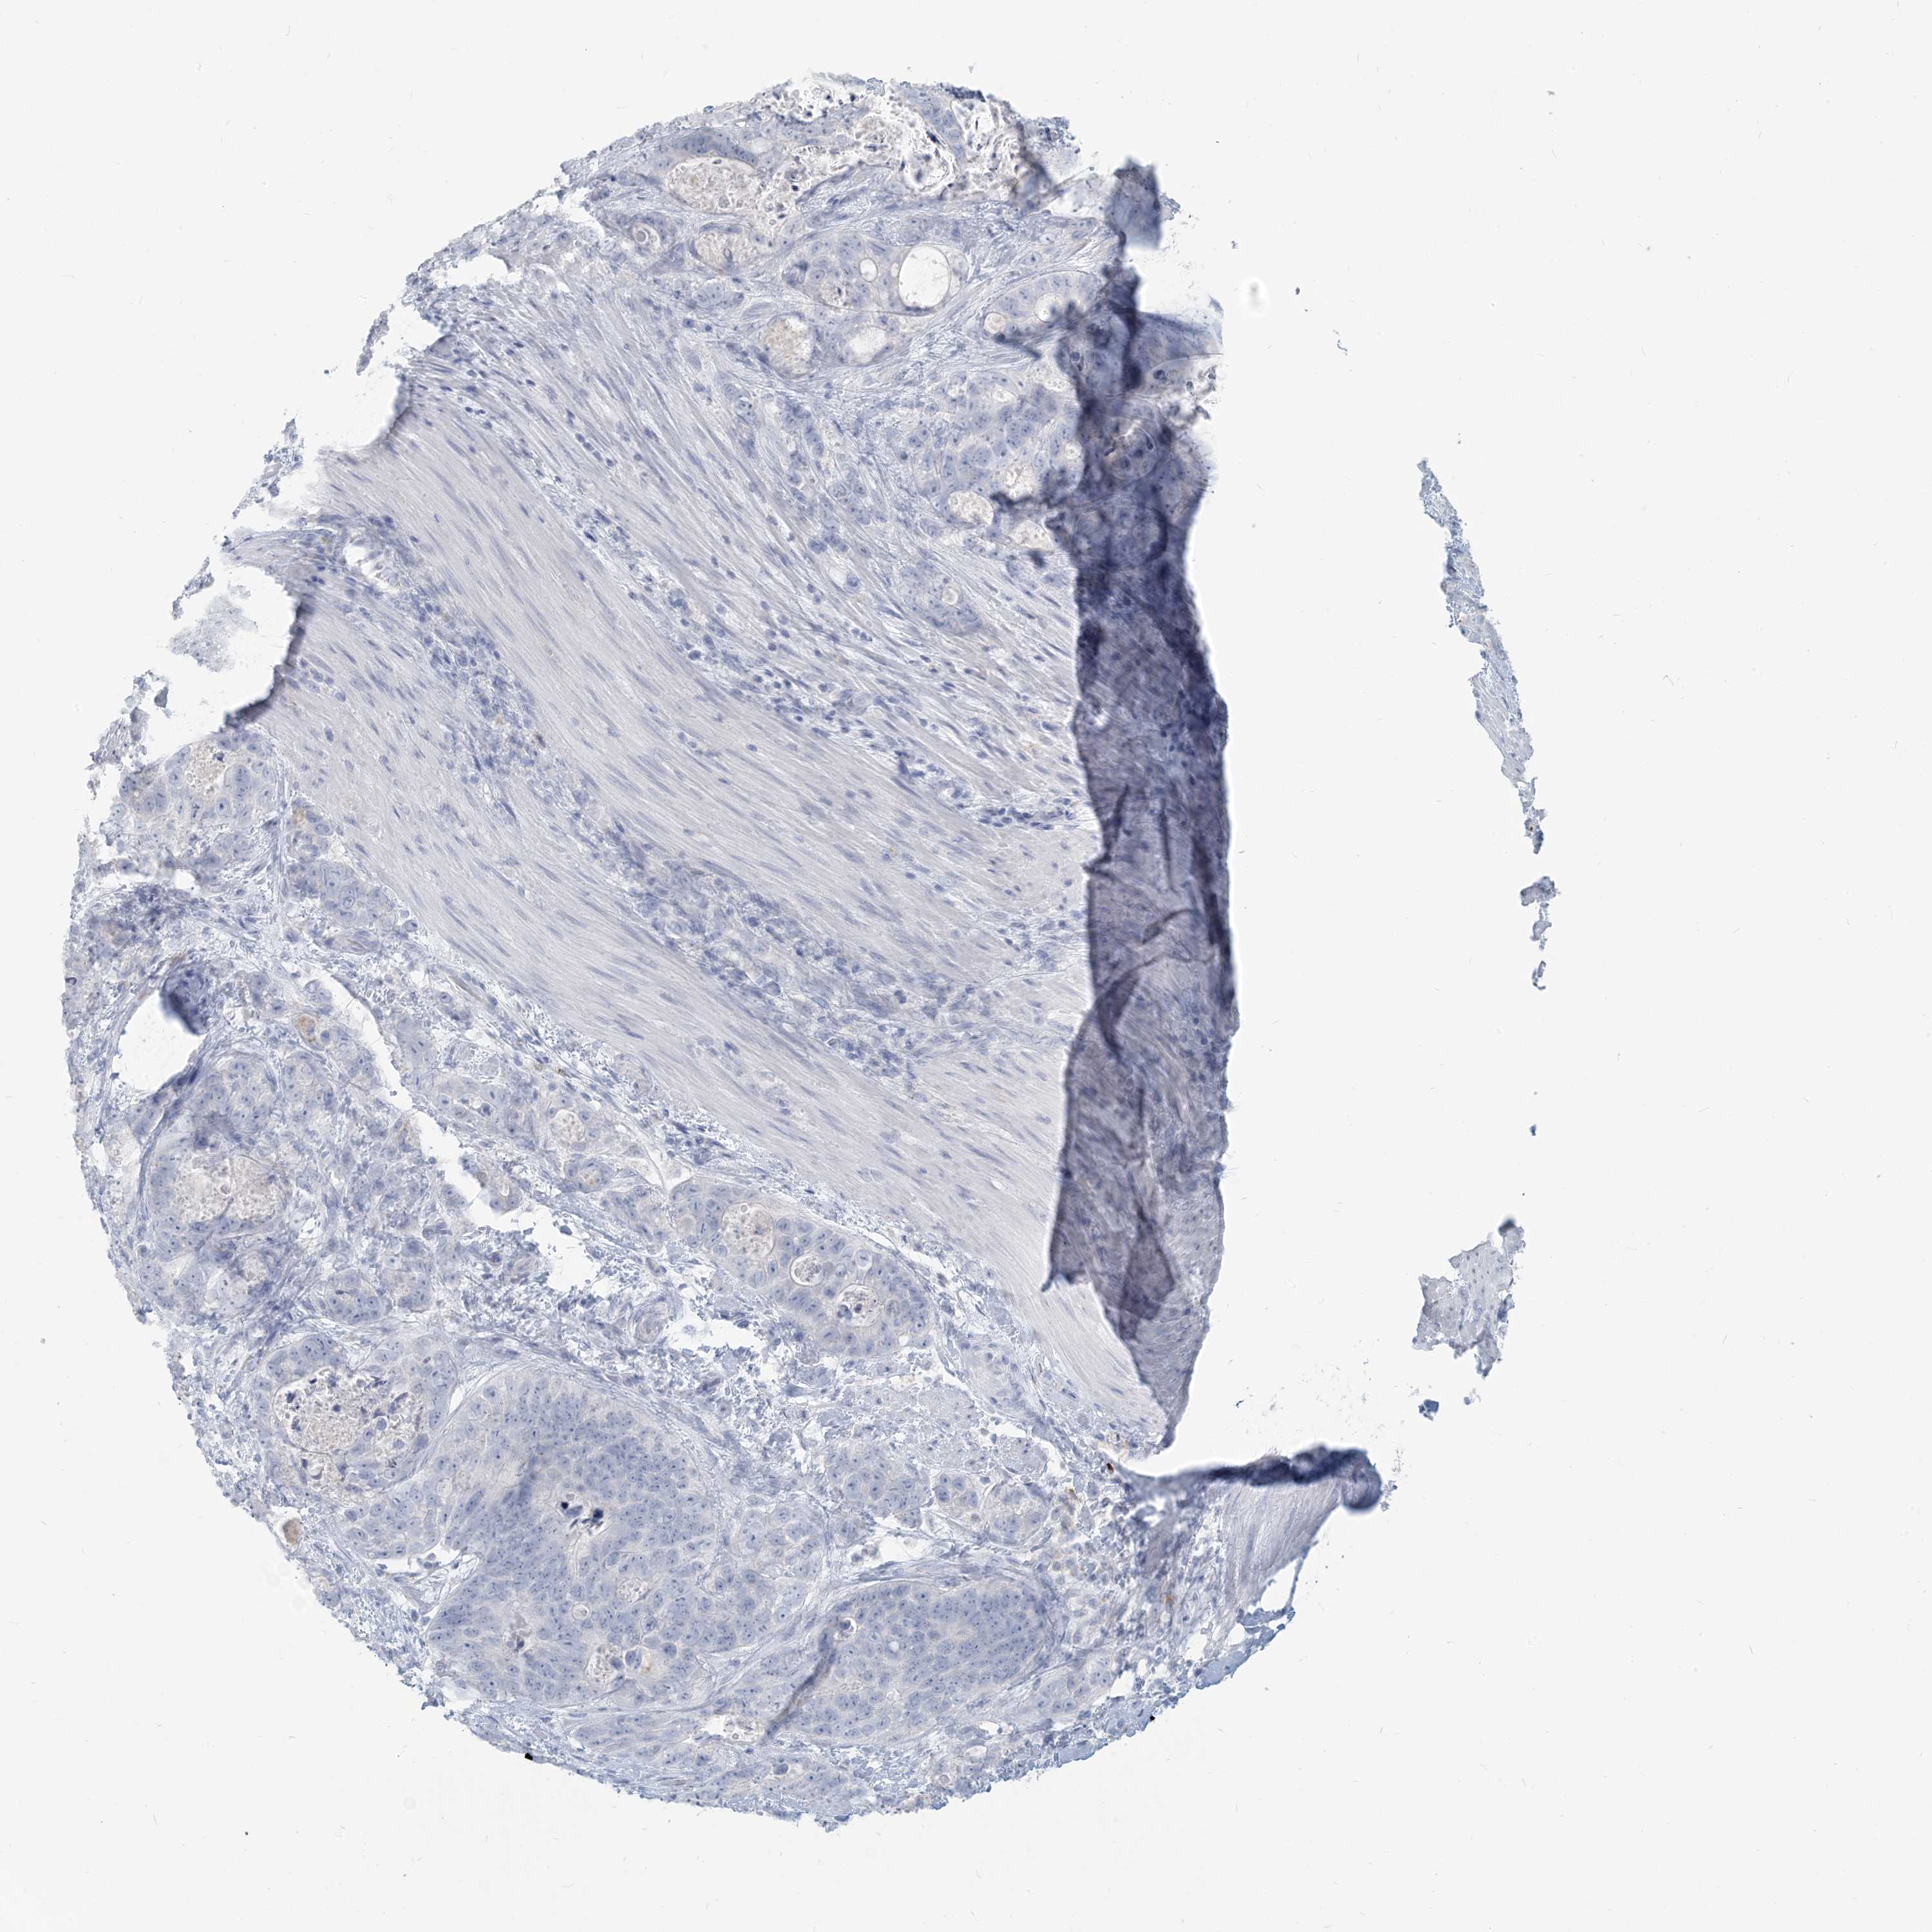

STOMACH CANCER - Protein expressioni

A mouse-over function shows sample information and annotation data. Click on an image to view it in a full screen mode. Samples can be filtered based on level of antibody staining by selecting one or several of the following categories: high, medium, low and not detected. The assay and annotation is described here.

Note that samples used for immunohistochemistry by the Human Protein Atlas do not correspond to samples in the TCGA dataset.

Antibody stainingi

Antibody staining in the annotated cell types in the current human tissue is reported as not detected, low, medium, or high, based on conventional immunohistochemistry profiling in selected tissues. This score is based on the combination of the staining intensity and fraction of stained cells.

Each image is clickable and will lead to virtual microscopy that enables deeper exploration of all samples and also displays staining intensity scores, fraction scores and subcellular localization as well as patient and tissue information for each sample.

Antibody HPA043151

Antibody CAB015400

Antibody CAB034021

Staining

High

Medium

Low

Not detected

Intensity

Strong

Moderate

Weak

Negative

Quantity

>75%

75%-25%

<25%

None

Location

Nuclear

Cytoplasmic/membranous

Cytoplasmic/membranous,nuclear

Adenocarcinoma, NOS